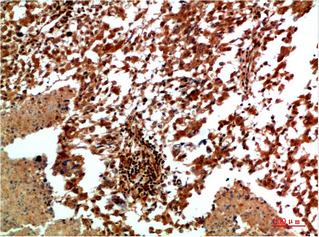

JNK2 Rabbit Polyclonal Antibody

WB, IHC, IF

WB 1:500-2000; IHC 1:50-300; IF 1:50-200